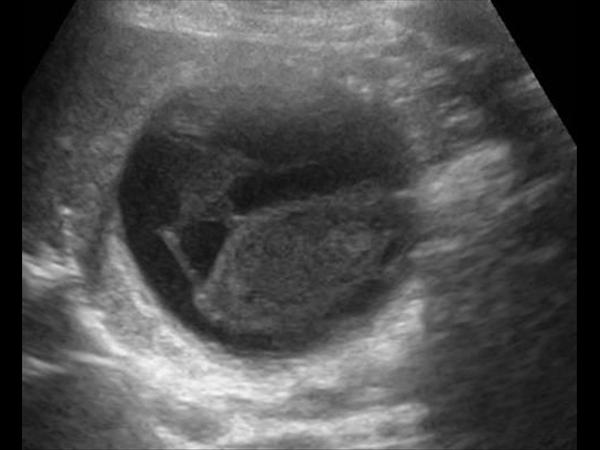

Chảy máu túi mật

Chảy máu túi mật - Ảnh 3

» Thông tin: Nữ giới – 81 tuổi.

» Lâm sàng: Đau mạn sườn phải / Sau thủ thuật ERCP.